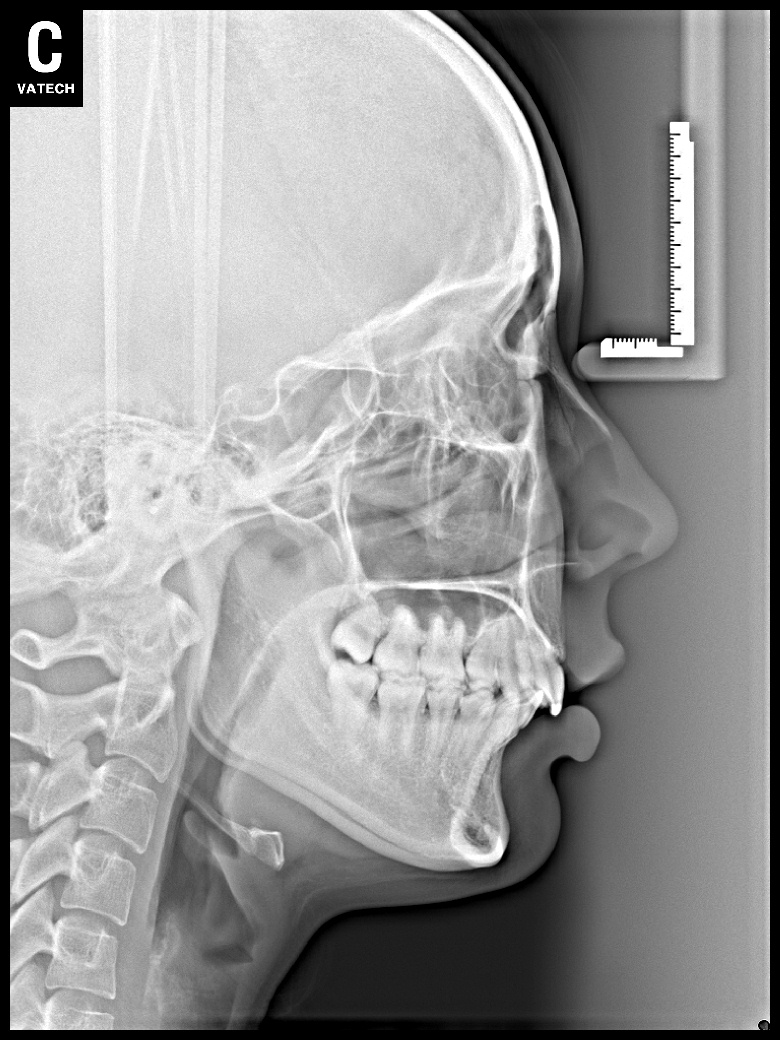

치료 후 사진입니다.